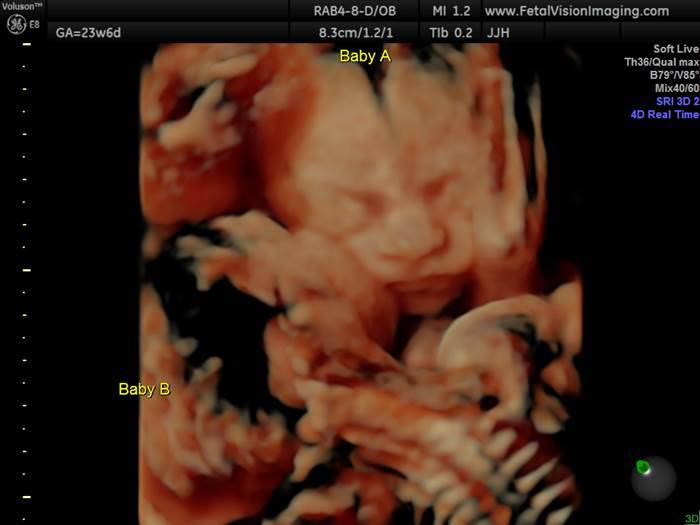

La ventiduenne mamma e il suo compagno Randy Good stavano si trovavano presso il Fetal Vision Imaging e, durante l’ecografia alla 25esima settimana hanno visto le loro due gemelline, Bella e Callie, ancora nell’utero materno mentre si scambiavano alcune coccole.

“Bella stava baciando Callie su una guancia e dopo hanno iniziato a baciarsi, è stato bellissimo da vedere”.

Nelle precedenti ecografie però le bimbe erano separate, una nella parte bassa dell’utero e una nella parte alta. “In un’occasione Bella stava dando calci in faccia a Callie e Callie stava cercando di succhiarle un dito”.